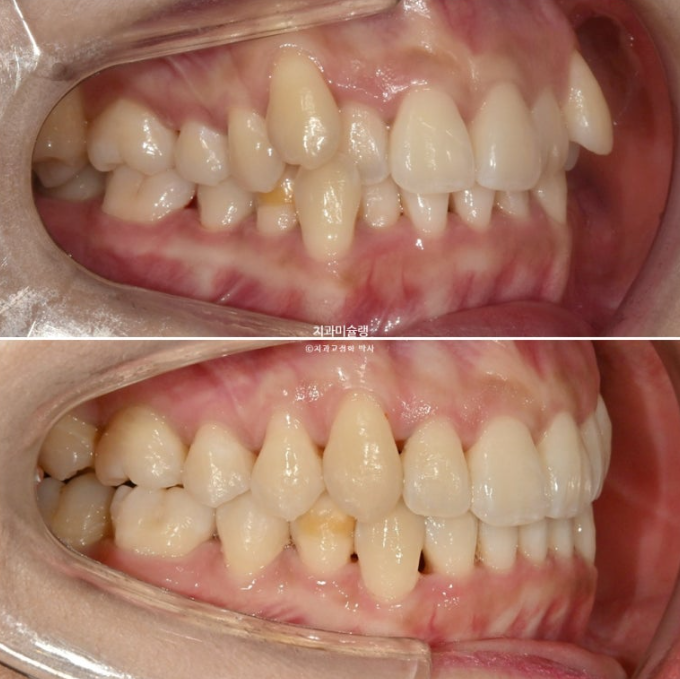

23.08-25.10

23.08~25.10

상악 제2대구치 발치공간을 이용하여 송곳니 덧니를 배열했습니다.

사랑니는 발치한 두 번째 큰어금니 자리를 잘 채워주고 있습니다.

하악 사랑니 공간을 이용하여 덧니를 배열했습니다.